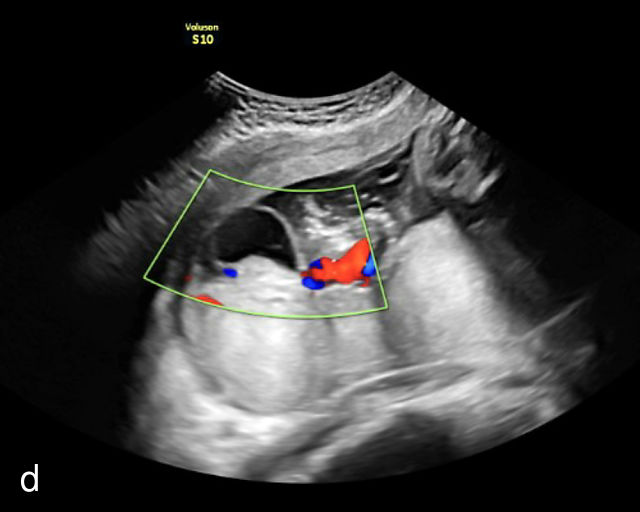

Placental chorioangiomas

The typical sonographic appearance of a chorioangioma on grayscale ultrasound is a well-circumscribed mass arising from the fetal surface of the placenta, protruding into the amniotic cavity, and distinctly separate from the placenta (Figure 12; Video 7). These tumors are most commonly located near the umbilical cord insertion site on the placenta. Sonographically, they may appear hypoechoic or hyperechoic and are often heterogeneous, with possible calcifications, hemorrhage or infarction visible within the mass.9 The appearance of these masses may change over time.141 Color flow Doppler imaging typically reveals vascularity within the tumor, showing low-resistance vessels and arteriovenous shunts (Figure 12c–e; Video 7).9 These shunts are believed to contribute to fetal complications such as high-output cardiac failure, anemia and hydrops.141 Three-dimensional ultrasound may be helpful in assessment of the mass.146 Importantly, the differential diagnosis includes placental hemorrhage, and color flow Doppler is essential to assist in making the diagnosis.

12

Grayscale (a,b), color Doppler (c,e) and power Doppler (d) images of chorioangiomas, showing heterogeneous masses protruding from the placental surface.